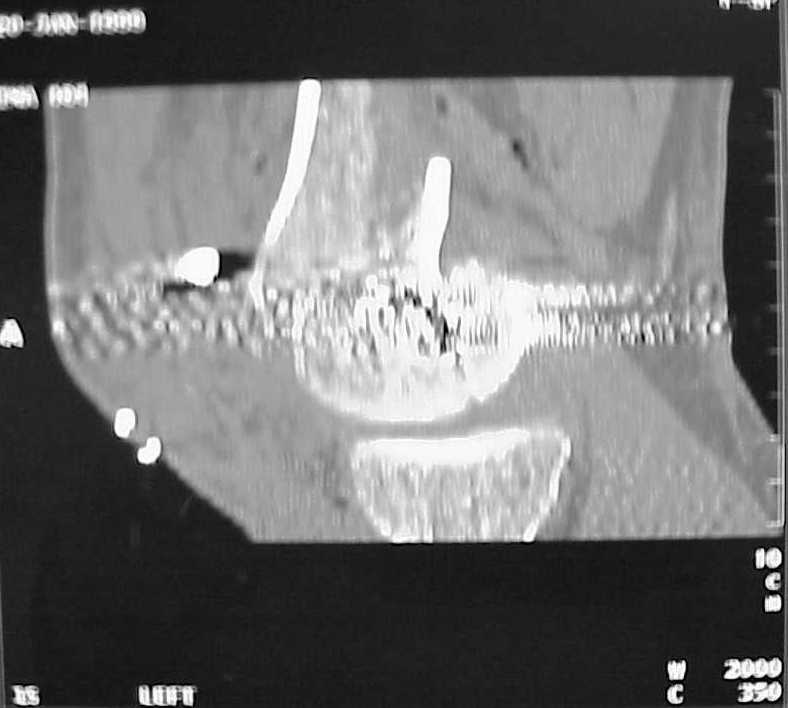

A CT and knee xrays would help identify lateral condyle comminution and/or a "hoffa fragment" of the posterior condyle. I am concerned that the lateral cortex is not sufficient to give purchase for a retrograde IMN. blocking screws could improve this as a possibility. A long blade or LISS if avaible would be my secondary choices. Good luck. Any chance you can get these cases transferred earlier when it

Lateral condyle looks too small for the blade, and the plate too short.

Use 6.5 mm cannulated screws if you have and

place one anterior to where IMN will go if anterior cortex if insufficient and AP screws on either side of the IMN out of the trochlea to provide some additional varus/valgus stability. I worry about the leg going into valgus w/the lack of lateral cortex.

See attached case that was done several years ago before LISS. He had comminuted trochlea and anterior blocking screws were used to prevent anterior IMN cut-out.